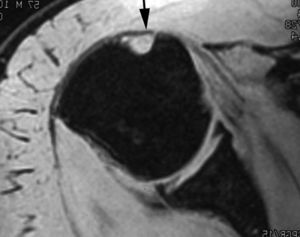

Lesión de Bankart

La lesión de Bankart se produce durante una dislocación anterior e inferior de la cabeza humeral, con impactación de la misma contra el borde anteroinferior de la glenoides, causando un arrancamiento del LG con rotura capsuloperióstica. Al mismo tiempo, se produce frecuentemente una fractura por impactación de la cabeza humeral (lesión de Hill Sachs) (fig. 9). En ocasiones, dicha lesión se acompaña de una fractura del borde anterior e inferior de la glenoides (Bankart óseo).

Fig. 9.--Lesión de Bankard y Hill-Sachs. Artrorresonancia axial T1, donde se observa un desprendimiento completo del labio glenoideo (flecha larga en A) con una rotura capsuloperióstica (cabezas de flecha en A). Nótese la fractura por compresión del margen posterosuperior de la cabeza humeral, representando una lesión de Hill-Sachs (flechas en B).